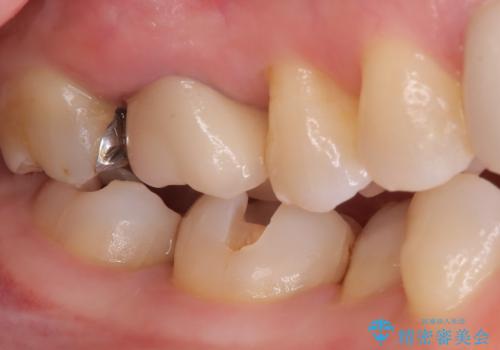

- 主訴:口を開けると所々入っている銀の詰め物が目立つので白い物にやり替えたい。

下顎大臼歯部に入っている保険適用のメタルインレーを、適合性と審美性の良いセラミックインレーでのやり替えとなりました。